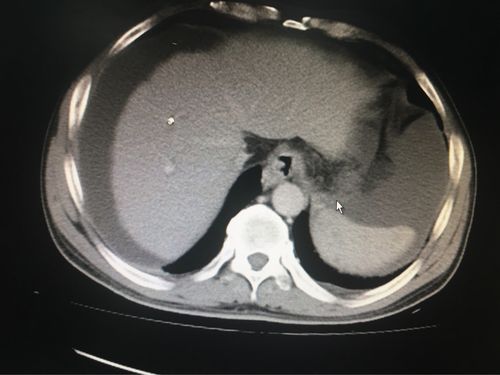

医生文章 正文 肝硬化主要ct表现: 1.

ct提示肝硬化,腹水,食管内可见扩张的血管

肝硬化CT